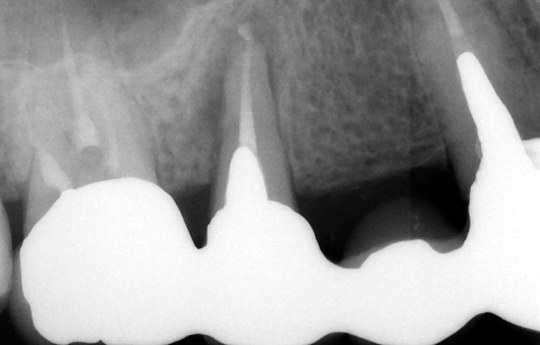

④インプラント埋入後

歯科用CTとインプラントシミュレーションソフトによる事前の治療計画

このようにインプラント予定部位に骨がなくても骨を作る(骨造成)ことができます

治療前

骨造成して完成

また、事前検査にも負担軽減の工夫をしています。インプラントを埋め込むあごの骨には、重要な神経や血管があり、そこを誤って傷つけるようなことがあってはなりません。そのような危険性をできる限り少なくするためには、術前の精密な検査や診断が重要となります。そこでCTによる検査を行うことで、手術中の事故を防ぎ、より安全に治療を行えるよう努めているのです。